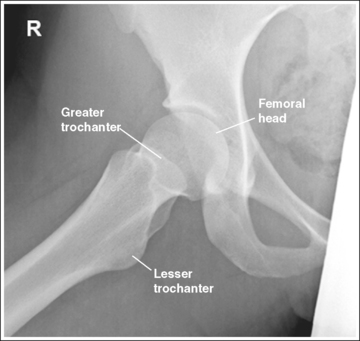

The femoral neck is demonstrated without foreshortening, the greater trochanter is in profile laterally, and the lesser trochanter is superimposed by the femoral neck.

• Accurate leg positioning. To demonstrate an AP hip projection with the femoral neck shown without foreshortening and the greater trochanter in profile, the patient's leg should be internally rotated until the foot is angled 15 to 20 degrees from vertical and the femoral epicondyles are positioned parallel with the imaging table (Figure 7-4; see Figure 7-1). A sandbag or tape may be needed to help the patient maintain this internal leg rotation.

The femoral head or neck is at the center of the exposure field. The acetabulum, greater and lesser trochanters, femoral head and neck, and half of the sacrum, coccyx, and symphysis pubis are included within the collimated field. Any orthopedic apparatus located at the hip are included in their entirety.

• A perpendicular central ray is centered 1.5 inches (4 cm) distal to the midpoint of a line connecting the ASIS and superior symphysis pubis, to center the hip joint in the center of the exposure field, and a perpendicular central ray is centered 2.5 inches (6.25 cm) distal to the midpoint of a line connecting the ASIS and superior symphysis pubis to place the femoral neck in the center of the exposure field (Figure 7-6). Center the IR to the central ray and open the longitudinal collimation enough to include the ASIS and any hip orthopedic apparatus. Transversely collimate to the patient's midsagittal plane and within 0.5 inch (1.25 cm) of the lateral hip skin line. Including half of the sacrum, coccyx, and symphysis pubis within the exposure field provides a way to evaluate pelvic rotation.

The femoral neck is demonstrated without foreshortening. The proximal aspects of the greater and lesser trochanters are demonstrated at approximately the same transverse level.

The lesser trochanter is in profile posteriorly, and the greater trochanter is superimposed by the femoral shaft.

• Rotation of the patient's affected leg determines the relationship of the lesser and greater trochanter to the proximal femur on an axiolateral hip projection. In general, when a patient is placed on the imaging table and the affected leg is allowed to rotate freely, it is laterally (externally) rotated.

• Effect of leg rotation on proximal femur visualization. To position the proximal femur in a lateral projection (90 degrees from the AP projection), demonstrating the lesser trochanter in profile posteriorly and superimposing the greater trochanter by the femoral shaft, the affected leg must be internally rotated until an imaginary line drawn between the femoral epicondyles is positioned parallel with the imaging table. The patient's foot is angled internally 15 to 20 degrees from a vertical position (Figure 7-18). If the affected leg is not rotated internally, the greater trochanter is demonstrated posteriorly and the lesser trochanter is superimposed over the femoral shaft (see Image 14). How much greater trochanter is demonstrated without femoral shaft superimposition depends on the degree of external rotation. Greater external rotation increases the amount of greater trochanter shown.